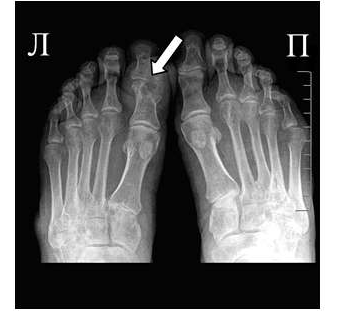

Для подагрического артрита характерно преимущественное поражение дистальных отделов стоп с преобладанием изменений в области I плюсне-фаланговых сочленений, реже изменения выявляются в мелких суставах кистей. При остром подагрическом артрите рентгенологические изменения, как правило, отсутствуют. Поэтому речь идет об изменениях, характеризующих хроническую стадию болезни. Типичным для хронического подагрического артрита является обнаружение узловых образований (тофусов) в костях в виде кистовидных просветлений и участков повышения плотности мягких тканей в области фаланг пальцев кистей и стоп. Деструкция костной ткани в виде эрозий, часто выявляемая при хроническом течении подагры, локализуется в основном на краях эпифизов костей и в дальнейшем распространяется на центральные отделы суставов.

Эрозии при подагрическом артрите имеют округлую или овальную форму, часто со склеротическим ободком. Склеротический ободок вокруг внутрисуставного тофуса создает типичный для подагрического артрита симптом «пробойника» (см. рис. 1).

В отличие от ревматоидного артрита и полиостеоартроза ширина суставной щели при подагре обычно сохраняется в норме даже в поздних стадиях заболевания. Также для хронической стадии, в отличие от ревматоидного артрита, не характерен остеопороз. Таким образом, I плюснефаланговый сустав наиболее характерная локализация при подагрическом артрите.

Рис. 2 Симптом «пробойника» в головках плюсневых костей обеих стоп в сочетании с вальгусной девиацией I плюсне-фаланговых суставов

Эрозии часто обнаруживаются в верхней и медиальной части плюсневой головки и часто в сочетании с вальгусной девиацией суставов. Типичным является асимметричность изменений (рис. 2).